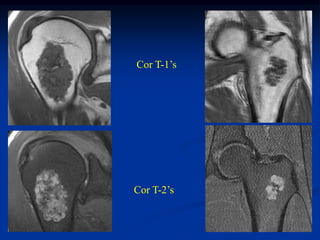

Case #554.2                Double enchondroma

52 year old male with incidental findings in R shoulder & L hip

Bone scan

Cor T-1’s

Cor T-2’s